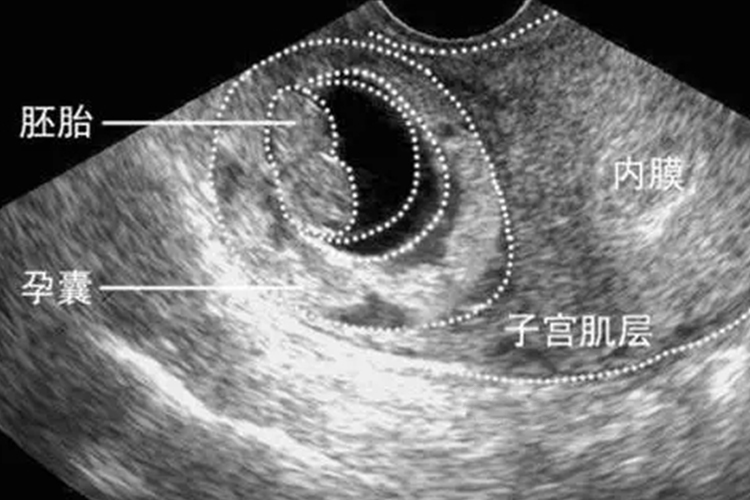

- 第三代试管婴儿技术,即胚胎植入前遗传学检测(PGT),旨在通过遗传学检测筛选出健康的胚胎进行移植,从而提高试管婴儿的成功率和降低遗传病的风险。在此过程中,囊胚是胚胎发育的一个重要阶段,通常只有发育良好的胚胎才能形成囊胚。